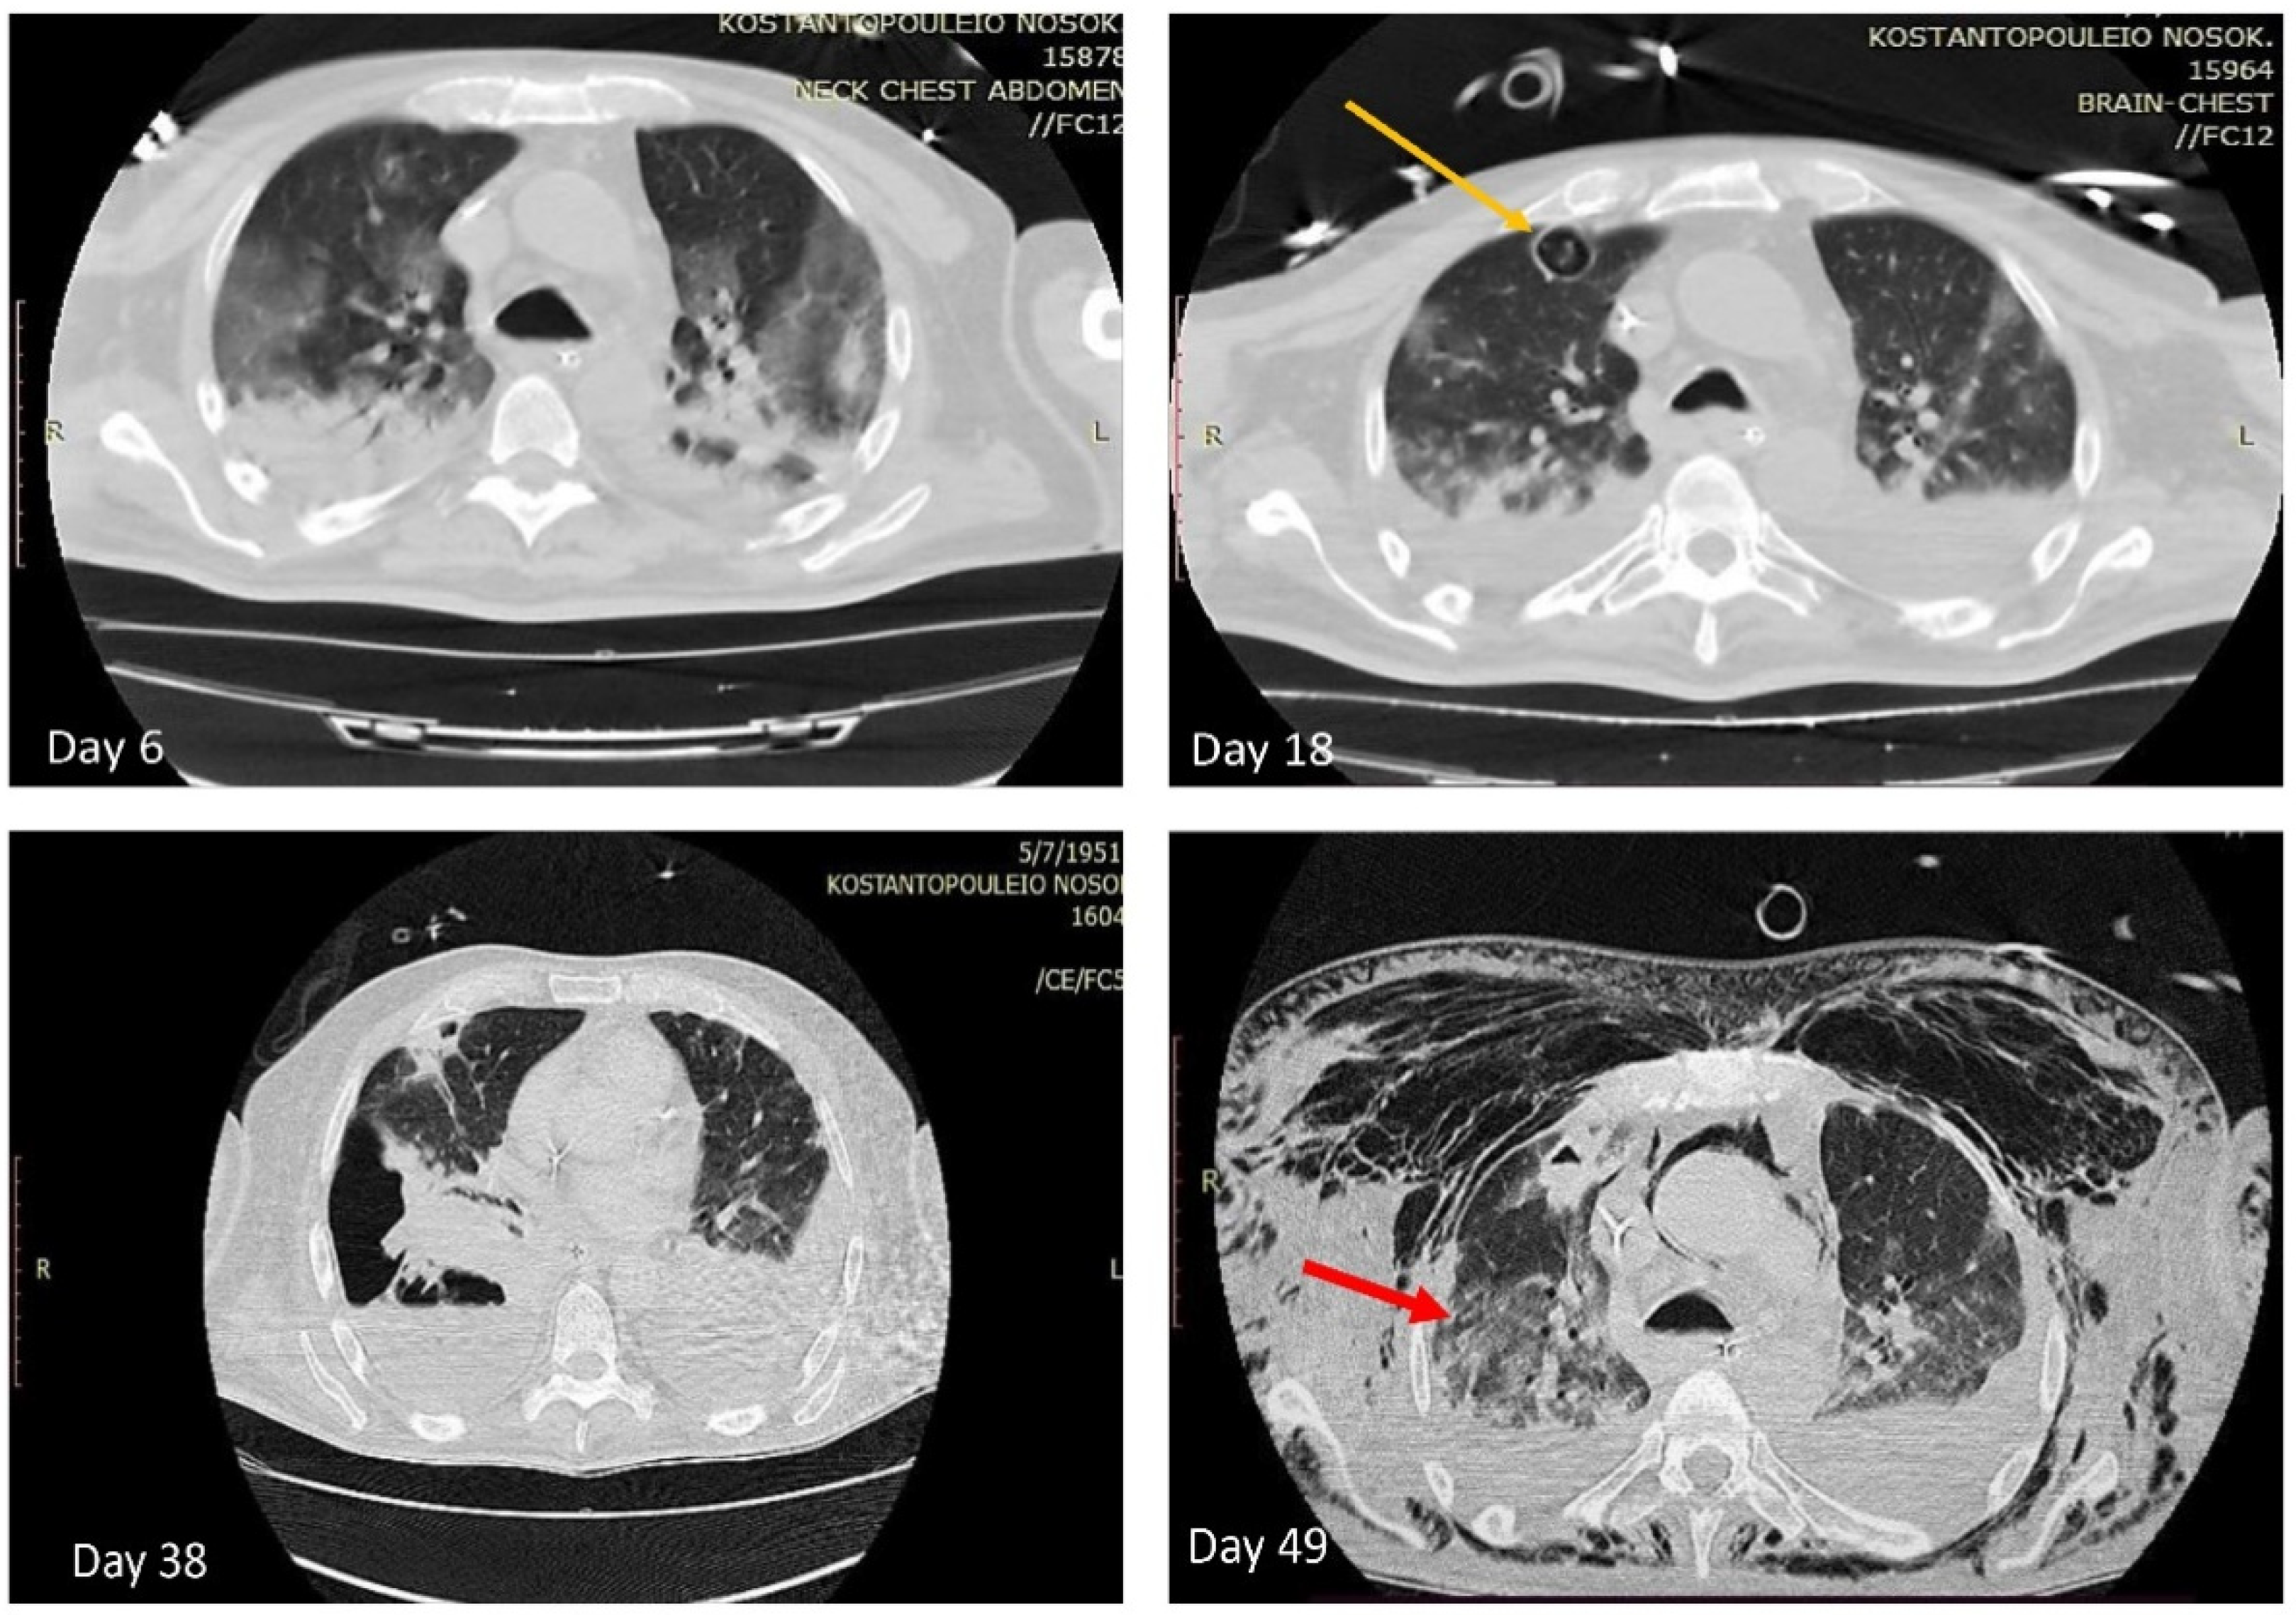

Susceptibility to antifungal agents was evaluated by the EUCAST standardized broth microdilution method (Aspergillus spp. EUCAST Antifungal Clinical Breakpoints Table v. 10.0 valid from 4 February 2020) [23]. MIC values of ≥128 μg/mL for fluconazole, 0.25 μg/mL for itraconazole, 0.5 μg/mL for voriconazole, 0.25 μg/mL for posaconazole, 4 μg/mL for flucytosine, 1 μg/mL for amphotericin B, and >8 μg/mL for all echinocandins (caspofungin, anidulafungin, micafungin) were obtained. The patient was administrated with voriconazole on day 6 and computed tomography (CT) was performed (Figure 2), which revealed bilateral ground glass opacities and consolidations of dependent parts of lung parenchyma.

Figure 2.

Chest computed tomography (CT) showing multi-lobar peripheral ground-glass opacities and consolidations (day 6); the yellow arrow depicts one cavitary lesion (day 18); the red arrow depicts the bronchopleural fistula (day 49).

Being on treatment, another CT scan was performed on day 18 (Figure 2), which disclosed three cavitary lesions with diameter up to 2.2 cm at upper and middle lobe of the right lung and liposomic amphotericin B was added for treatment. At serial CT scans the cavitary lesions remained unchanged, while the patient presented pulmonary embolism (day 26), pyopneumothorax (day 38), and bronchopleural fistula (day 49) (Figure 2). Culture of the corresponding pleural effusion (day 38) revealed only the pandrug-resistant A. baumannii and the patient started on another course of meropenem, tigecycline, and colistin. Notably, A. niger was not isolated from subsequent samples of tracheal aspirates. However, his weaning from mechanical ventilation was not accomplished, due to damage of lung parenchyma along with critical illness polyneuropathy and myopathy and tracheostomy was performed. Moreover, his clinical condition deteriorated and finally he died on day 60, due to septic shock and multi-organ failure.